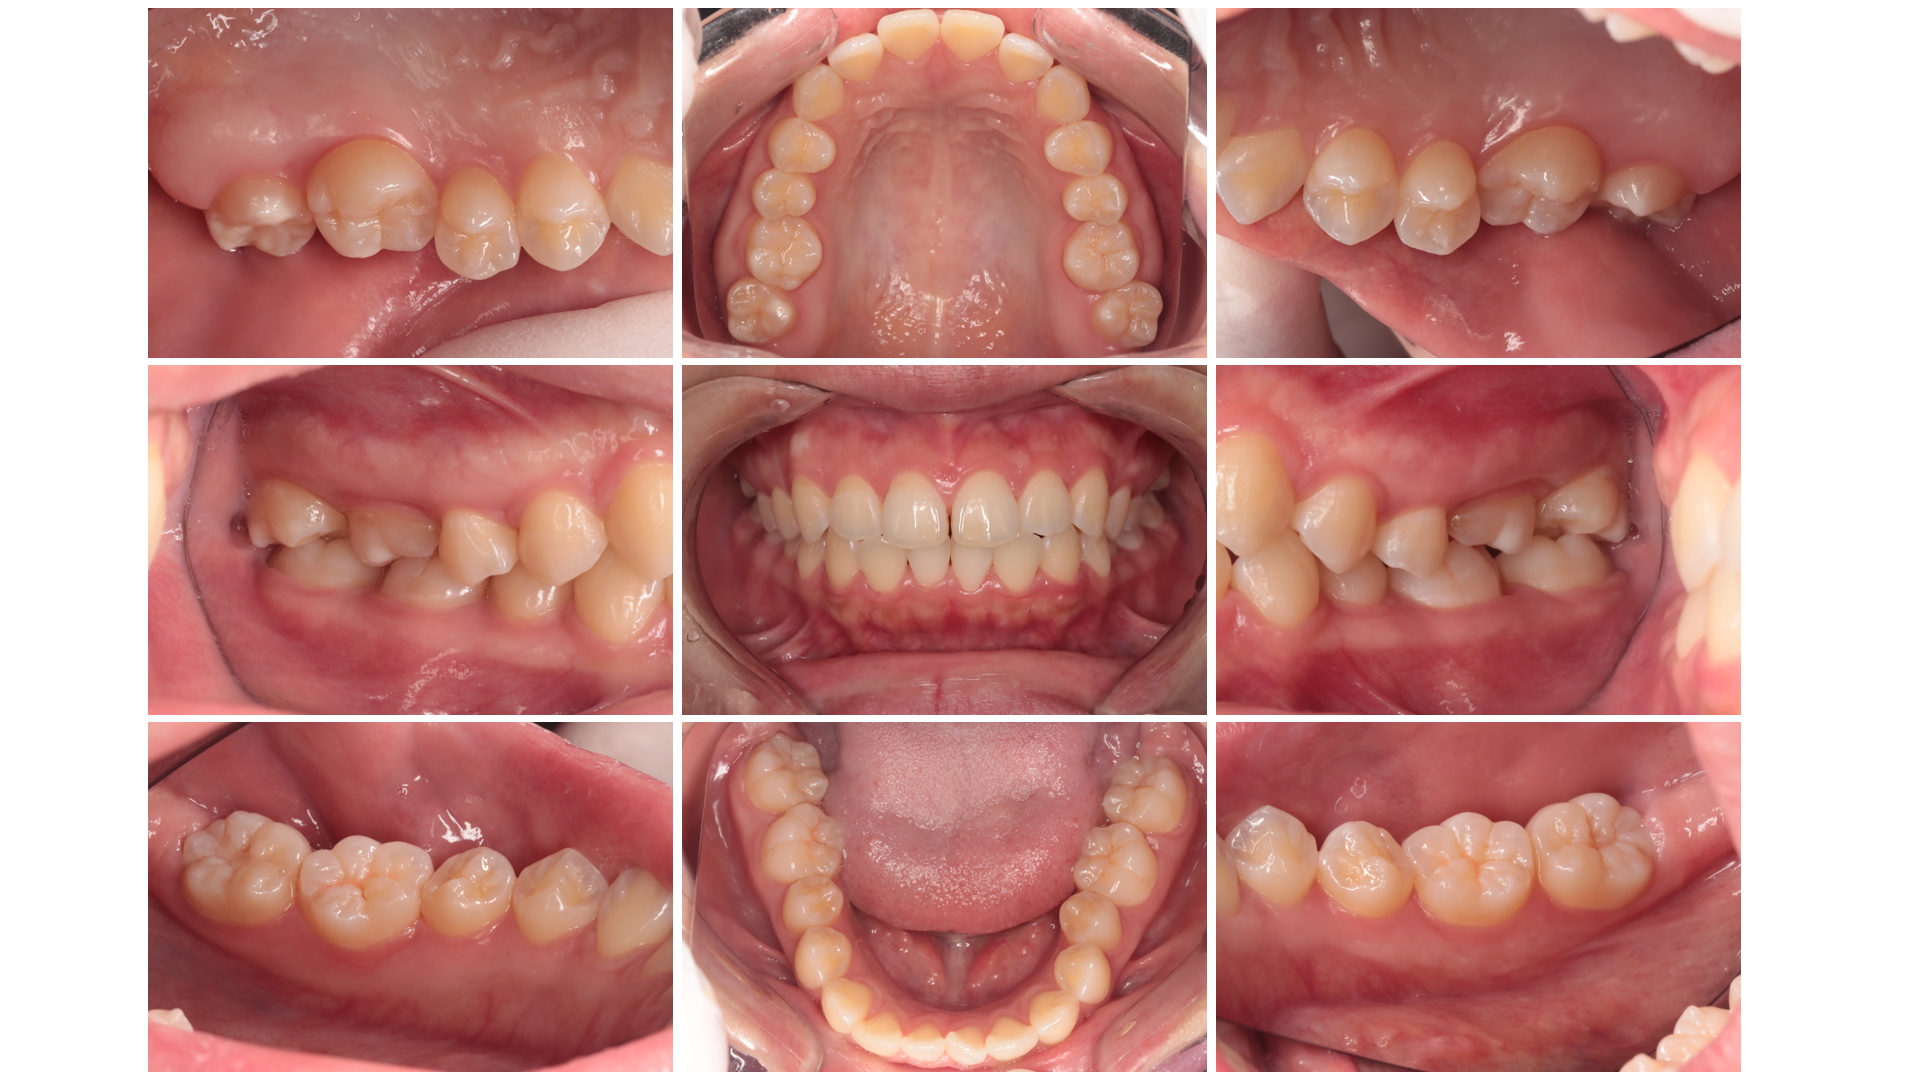

精密検査と診断

まず、現在のお口の状態を詳しく把握するため、レントゲン撮影や歯周ポケットの深さの測定、口腔内写真撮影などを行います。これらの検査結果に基づき、歯周病の進行度や原因を正確に診断し、患者さん一人ひとりに最適な治療計画を立案します。

レントゲン撮影口腔内写真撮影